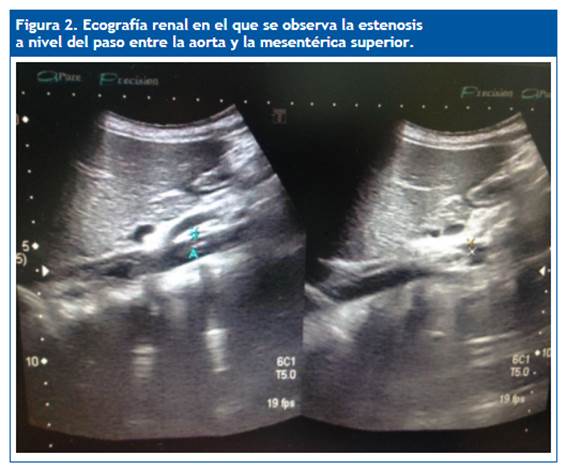

Ante la recurrencia de los episodios y la ansiedad familiar, se decide programar una biopsia renal. Previamente se realiza una ecografía, que detecta la compresión de la vena renal izquierda entre la aorta y la arteria mesentérica superior (Fig. 1 y Fig. 2). Se realiza una angiotomografía renal (Fig. 3) en la que se confirma el diagnóstico de síndrome de cascanueces anterior.

La ecografía Doppler puede ser usada como primera opción ante la sospecha de esta patología. La angiotomografía renal y la angiorresonancia permiten visualizar la anatomía y pueden demostrar con precisión el punto de compresión de la vena renal izquierda y/o la dilatación preestenótica de la vena junto con varices perirrenales o gonadales. La venografía retrógrada es el gold standard del diagnóstico. No solo confirma los cambios anatómicos sino los gradientes de presión. Es la prueba diagnóstica que aporta más información, pero se trata de una prueba invasiva. Solo se realiza si se presentan síntomas graves7,8.